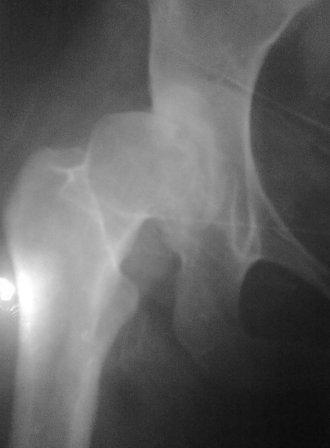

Уважаемые коллеги! Обратилась б-ная 26лет с сильными болями в лев. т/б суставе,

оказалась в 2х летнем возрасте лечилась у меня по поводу врожд.вывиха бедер. Боли начались 2 года назад после второй беременности. Сгибание в т/б суставе 90градусов,разгибание-10,отведение-30.приведение - 10, внутрен.ротация - 20., наруж. ротация - 10. при отведении и ротации боли усиливается. Направил в НИИТО, где ей предлагали эндопротезированию, но финансовые возможности не позволяет.

Предварительный план: учитывая неплохое функциональное состояния т/б сустава межвертельная укорачивающая, варизирующая и возможно деротационная остеотомия с фиксацией клинковой пластиной, или PF БИОС (по предварительным скиаграммам и КТ)